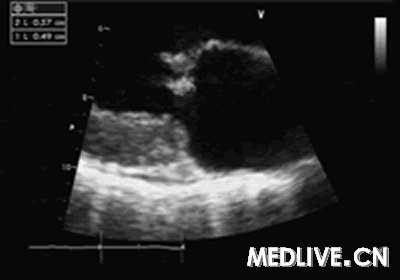

行冠状动脉造影发现:左前降支中远端局限性狭窄,约70%,左回旋支、右冠状动脉未见狭窄及斑块。超声心动图(UCG,图1):二尖瓣脱垂,轻度二尖瓣关闭不全,二尖瓣前叶赘生物4.9mm×5.7mm;节段性室壁运动异常(左室间隔下段,心尖部)。

图:超声心动图示——二尖瓣脱垂,轻度二尖瓣关闭不全,

二尖瓣前叶赘生物4.9mm×5.7mm;节段性室壁运动异常。